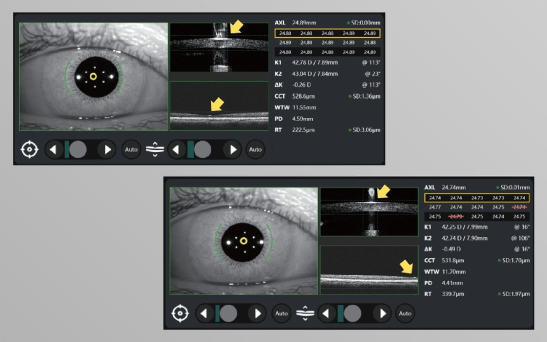

Автоматична перевірка фіксації в режимі реального часу

Точність вимірювання аксіальної довжини (AXL) залежить від надійної фіксації, що є складним завданням при роботі з дітьми. Colombo IOL вирішує цю проблему завдяки автоматичній перевірці фіксації в режимі реального часу, запобігаючи помилковим вимірюванням.